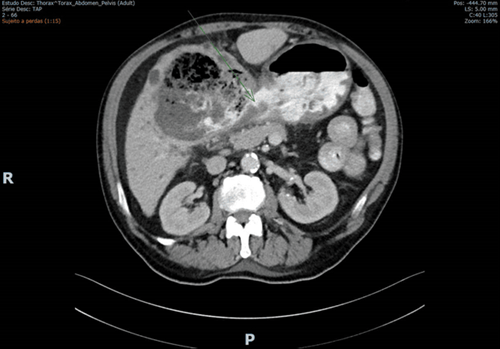

Due to the findings, a C.T. scan was requested (shown in Figure 1 and Figure 2). Several biliary hepatic cysts with varying dimensions were noted, but no hepatic solid lesions were detected. The liver segments IV and V presented with an 11.5 x 9.7 cm non-pure liquid collection, with gastric communication, evidenced by multiple air bubbles and oral contrast. Periceliac and perigastric ganglia were noted. No relevant findings were detected in the thoracic study or the remaining abdomen and pelvis.

Figure 1 CT scan with oral contrast administration showing a hepatic collection containing air and oral contrast.